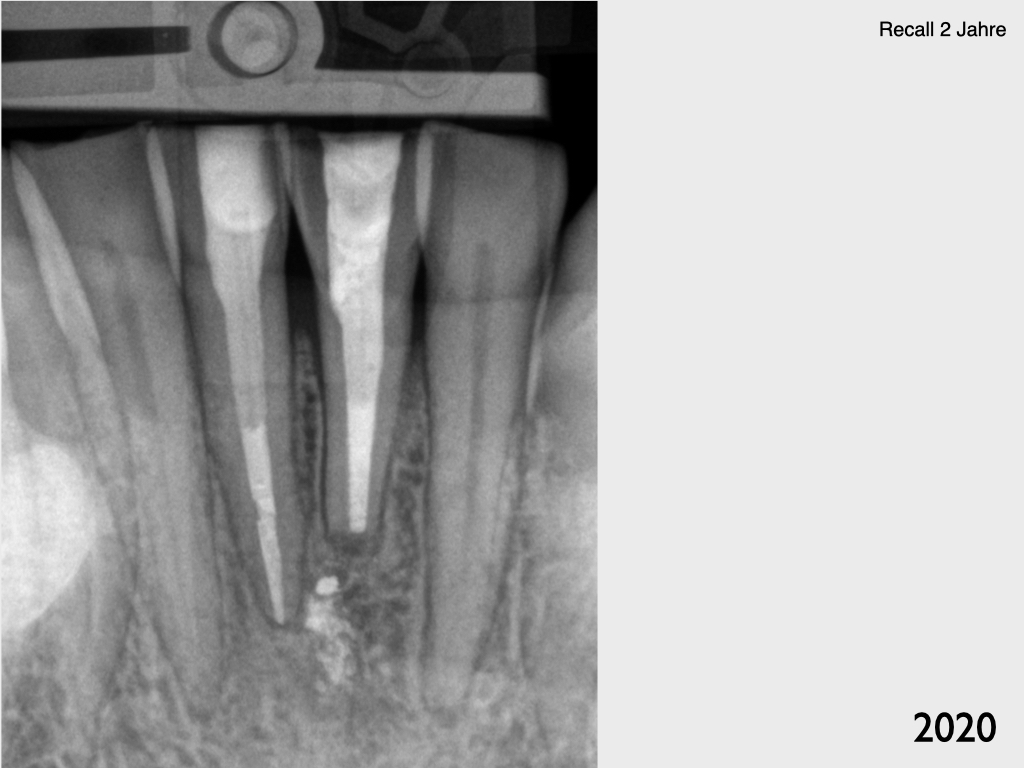

Und wieder ein UK Frontzahn